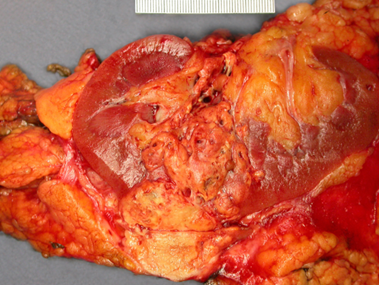

Đại thể

Thường là khối u vỏ thận một bên và đơn ổ, kích thước trung bình khoảng 7 cm. Khối u thường có ranh giới rõ, được bao quanh bởi giả bao u, phát triển theo kiểu đẩy nở và lồi ra từ vỏ thận. Hình thái đại thể đa dạng với thành phần đặc và nang, kèm các vùng xơ hóa màu xám và các ổ xuất huyết mới hoặc cũ màu nâu; hoại tử và biến đổi nang gặp thường xuyên. Khối u có màu vàng ánh kim do hàm lượng lipid cao; các khối u có độ mô học cao hơn có thể không có màu vàng do hàm lượng lipid và glycogen thấp hơn. Các vùng mềm, dạng thịt có thể phản ánh sự hiện diện của biệt hóa dạng sarcomatoid. Thường xuyên ghi nhận xâm lấn tĩnh mạch thận và xoang thận. Tổn thương hai bên và đa ổ là đặc điểm gợi ý bệnh lý di truyền.

Hình 2. ccRCC đã xâm lấn mạc Gerotta (pT4)

Hình 3. ccRCC có màu vàng, giới hạn ở thận (pT1b)

Hình 4. ccRCC đa ổ, với diện cắt đại thể loang lổ, khối u màu vàng óng xen kẽ các vùng xơ hóa và xuất huyết. Các vùng mềm, dạng thịt, màu nâu nhạt đến trắng xám trong khối u có thể gợi ý sự biệt hóa sarcomatoid.